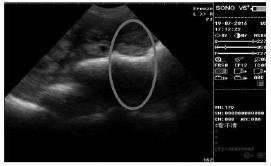

娠中期 (配种后 45 d~84 d) 是胎儿骨骼开始钙化到钙化完全的时期,由于羊水减少,孕囊变得不规则且不清晰 (见图 2),发育为胚胎,该时期的影像图上逐渐可见回声增强的白色强回声骨骼影像,80 d时,胎儿脊柱清晰显示。

图2 妊娠45 d图像